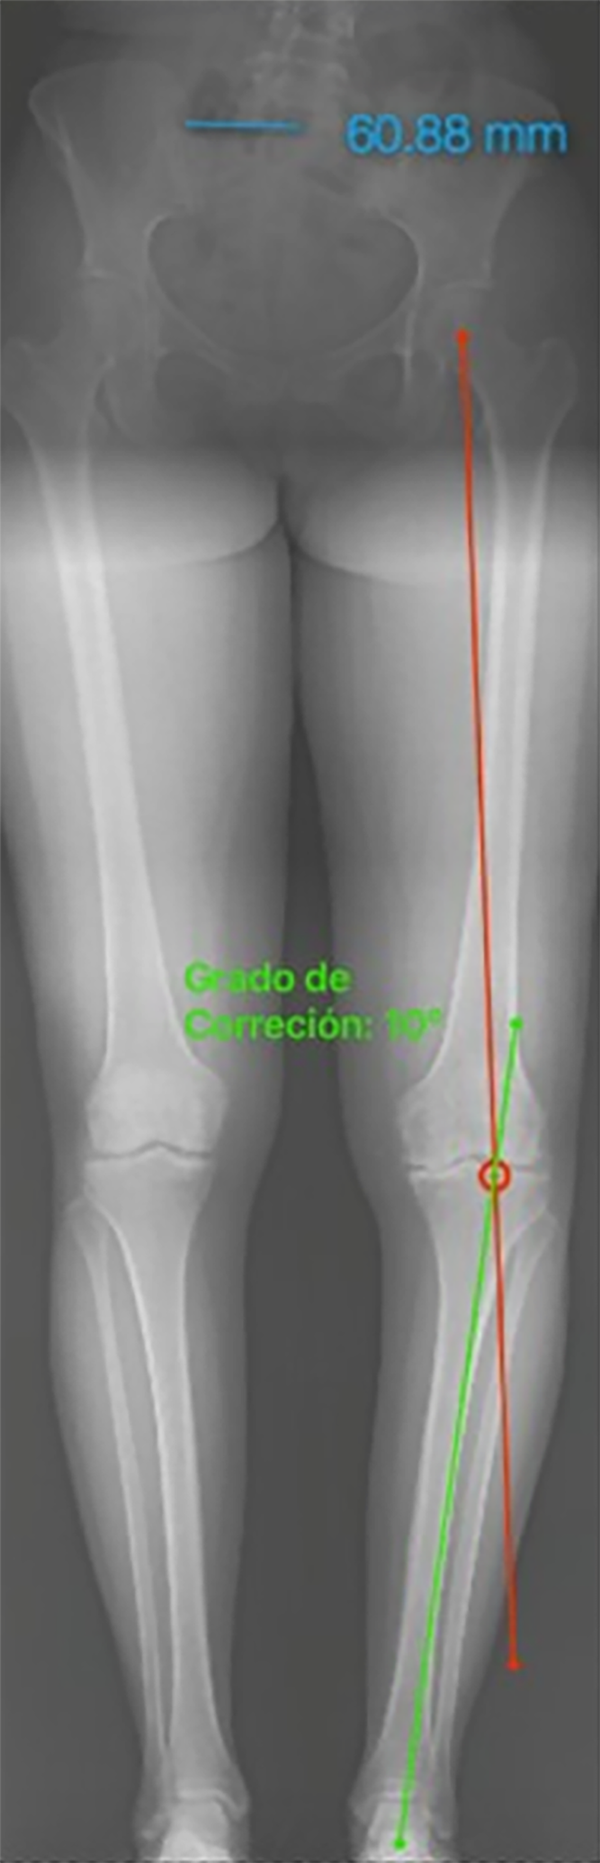

El paso 0 consiste en trazar una línea que va del centro articular de la cadera al centro articular del tobillo, recibe el nombre de “eje mecánico del miembro inferior” y el resultado fisiológico de esta medición es una línea que debe cruzar el centro articular de la rodilla con un rango de normalidad de desviación de 3 mm hacia medial o lateral.10 Al realizar la medición de la desviación, esta medida va a recibir el nombre de desviación del eje mecánico (MAD, por su nombre en inglés), según el cual, en caso de superar los 3 mm hacia medial, se trata de una deformidad en varo con un aumento de la carga en el compartimento medial de la rodilla; cuando el MAD se encuentra superior a los 3 mm laterales, es una deformidad en valgo y aumenta la carga del compartimento lateral de la rodilla21 (fig. 3).

Figura 3: Test de mal alineamiento: las líneas rojas corresponden al eje mecánico de los miembros inferiores, se marca el centro articular de la rodilla y se observa la desviación del eje mecánico o MAD derecho hacia medial de 24 mm, y en el izquierdo de 31 mm hacia medial, se evidencia una alteración de este valor con una deformidad en varo bilateral, con mayor predominio del lado izquierdo.

Noyes7 considera una mala alineación en varo cuando la línea de soporte de peso (weight-bearing line - WBL) cruza menos del 50% del ancho transversal desde medial hacia lateral de los platillos tibiales.7 Pero para otros autores, como Lobbenhoffer et al.,10 esta línea se conoce como eje mecánico de la pierna, o línea de Mikulicz, que conecta el centro de la cabeza femoral y el centro de la articulación del tobillo, considerada como fisiológica cuando se encuentra en promedio 4 mm (± 2 mm) medial al centro de la articulación de la rodilla. De esta manera, si el eje mecánico pasa lateral o medial a estos puntos, encontramos una deformidad en valgo o en varo, respectivamente (Tabla 1).